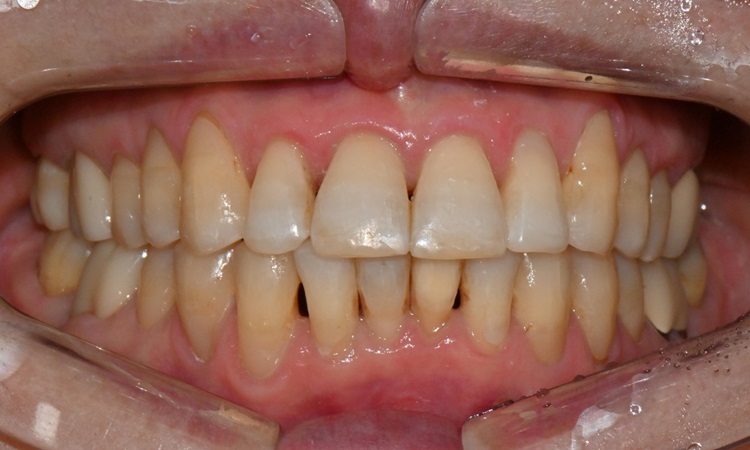

교정 치료 마무리 후

8개월 후 교정 치료가 마무리되었으며, 환자분께서 치아가 예쁘게 마무리되셨다며 매우 만족하셨습니다. 치간 삭제를 통해 black triangle도 일부 개선되었습니다. 미백 치료에도 관심이 있으셔서 2주 뒤 내원하셔서 미백 치료도 시행하셨습니다.